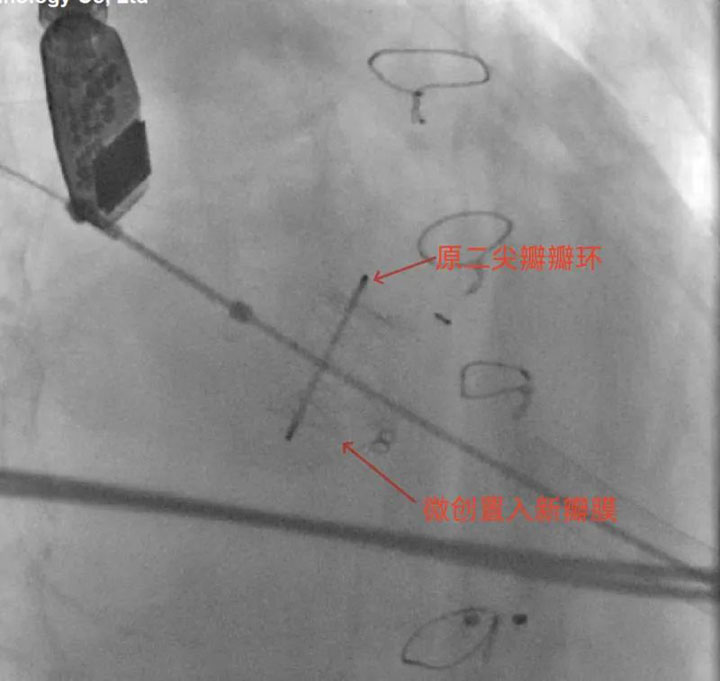

在胸心外科、麻醉科、导管手术室等多部门的通力配合下,经过约两个小时的操作,顺利将新的二尖瓣生物瓣膜释放至合适位置,成功完成经心尖二尖瓣“瓣中瓣”置换术。术后患者被转入ICU观察,第二天转回普通病房,目前,范阿姨已顺利出院,回访临床症状明显改善。